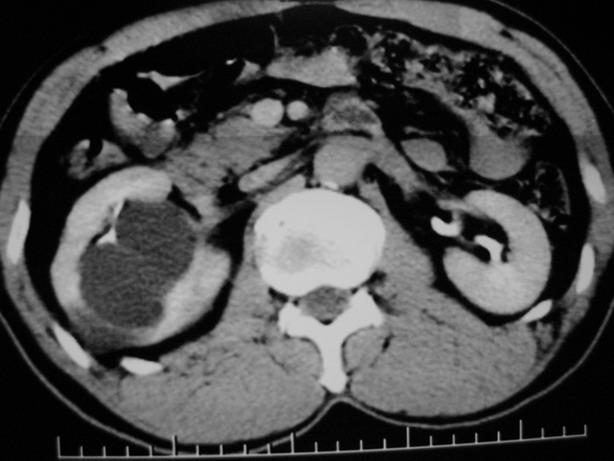

男性,48,体检发现,平时无症状。

平扫:

肾盂旁多囊性占位,有实性成分,增强有轻度强化,收集期病变内无造影剂显影。诊断肾盂旁囊肿,有实性成分无法解释,查书后诊断为:多房性囊性肾瘤!!不知大家同意否?????????对本病知道不多,望大家不吝赐教!!